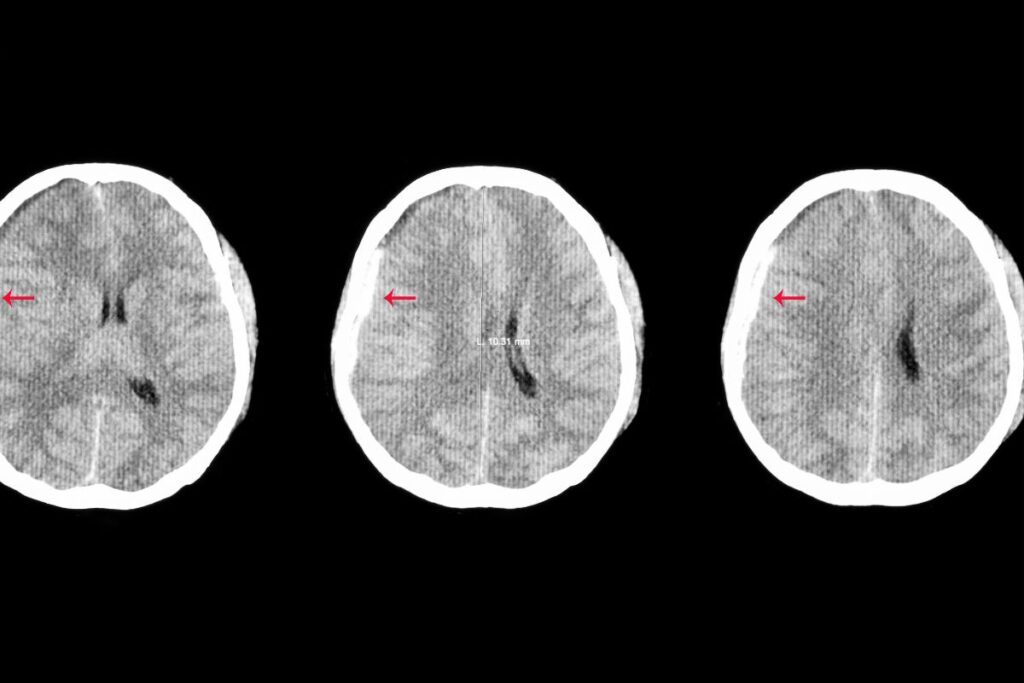

| Définition œdème osseux | Inflammation de la zone médullaire de l’os | Variable selon localisation | Nécessite IRM pour diagnostic précis |

L’œdème osseux, cette inflammation sournoise qui se niche dans la zone médullaire de l’os, représente une blessure fréquente chez les adeptes du trail. En tant que passionné de cette discipline exigeante, j’ai personnellement été confronté à cette pathologie après une course particulièrement technique dans les Alpes. Cette expérience m’a permis de comprendre l’importance d’une prise en charge rapide et adaptée.

La durée de guérison varie considérablement selon plusieurs paramètres essentiels. Le diagnostic précoce joue un rôle primordial dans le processus de récupération. Un œdème détecté rapidement, grâce à une IRM, permettra d’éviter les complications et d’accélérer la guérison.